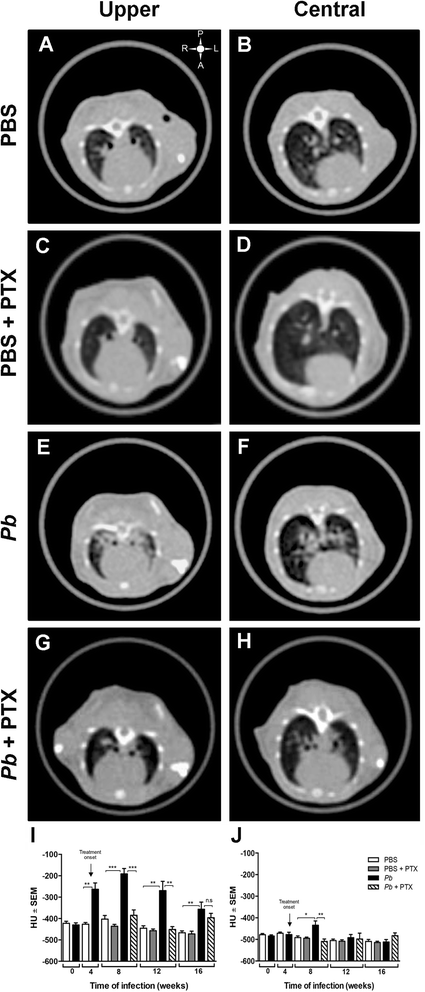

Fig. 1

PTX treatment decreases pulmonary density in Pb-infected mice. Representative HRCT images of upper and central pulmonary regions obtained from PBS-inoculated mice (a, b), PBS-inoculated mice treated with PTX (c, d), Pb-infected mice (e, f), and Pb-infected mice treated with PTX (g, h) at 12 weeks. Pulmonary density was measured in the lung parenchyma as described in the “Methods” section and is expressed as the mean of Hounsfield units (HU) ± SEM. i, j correspond to HUs measured in the upper (I) and central (J) lung regions at 0, 4, 8, 12, and 16 weeks. The upper right symbol in (a) gives the spatial position of posterior (P), anterior (A), left (L), and right (R) regions. n = 10 mice per group at each period of evaluation, *p <0.05; **p <0.01; ***p <0.001. ns not significant